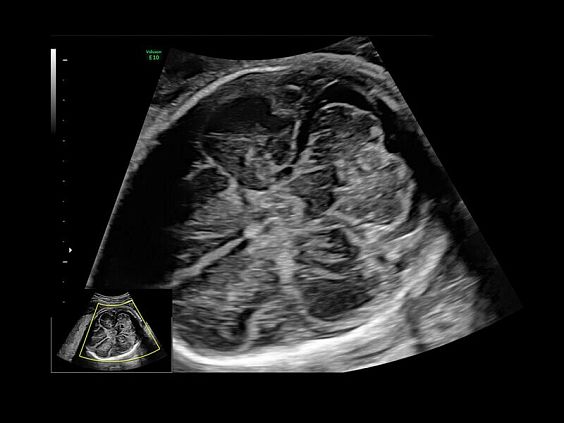

Клинические изображения

Современные клинические приложения и высокое качество изображений позволяют использовать Voluson E10 для наблюдения за ходом беременности максимально эффективно. С помощью этого аппарата можно проводить любые исследования, как рутинные, так и комплексные, выявляя проблемы на ранних стадиях и принимая своевременные меры.

• SonoVCAD heart (Sonography-based Volume Computer Aided Display heart) — программа формирует изображения сердца плода в стандартных проекциях в соответствии с международными рекомендациями на основе одного объемного изображения или данных 4D визуализации, полученных методом STIC.